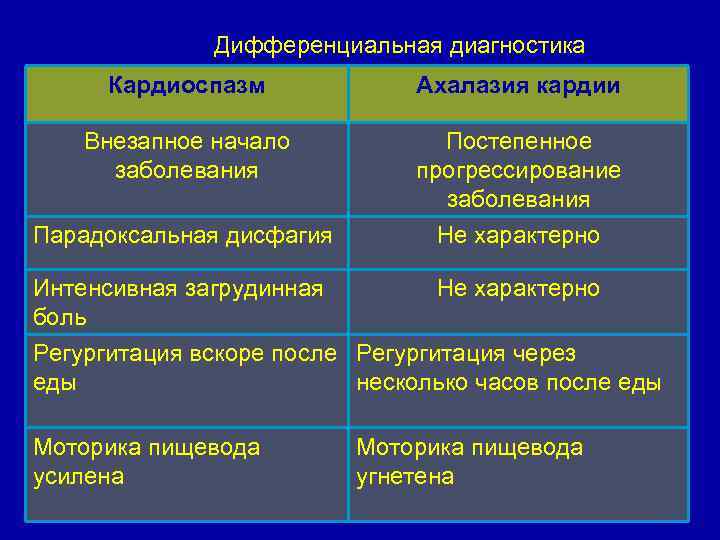

Дифференциальная диагностика Кардиоспазм Ахалазия кардии Внезапное начало заболевания Постепенное прогрессирование заболевания Парадоксальная дисфагия Не характерно Интенсивная загрудинная боль Не характерно Регургитация вскоре после Регургитация через еды несколько часов после еды Моторика пищевода усилена Моторика пищевода угнетена